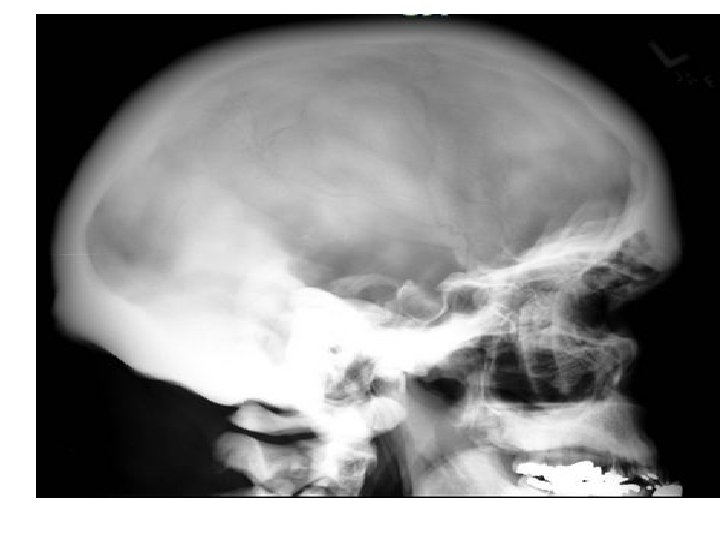

Osteopetrosis AKA: Albers-Schönberg Disease = Marble Bone Disease • Rare hereditary disorder with defective osteoclast function and overgrowth of bone: which become thick, dense and sclerotic results in brittle bones • Mandible : triangular opacity representing calcification within the secondary condylar cartilage ossification center. • Defective dentition with incomplete enamel formation and denatal caries.

• poorly pneumatized paranasal sinuses (ethmoid sinuses least severely affected) • Calvarium : high-attenuation inner table, a broad, lowattenuation diploic space, and a less high-attenuation outer table • Hair-on-end appearance : areas of increased haematopoietic activity.